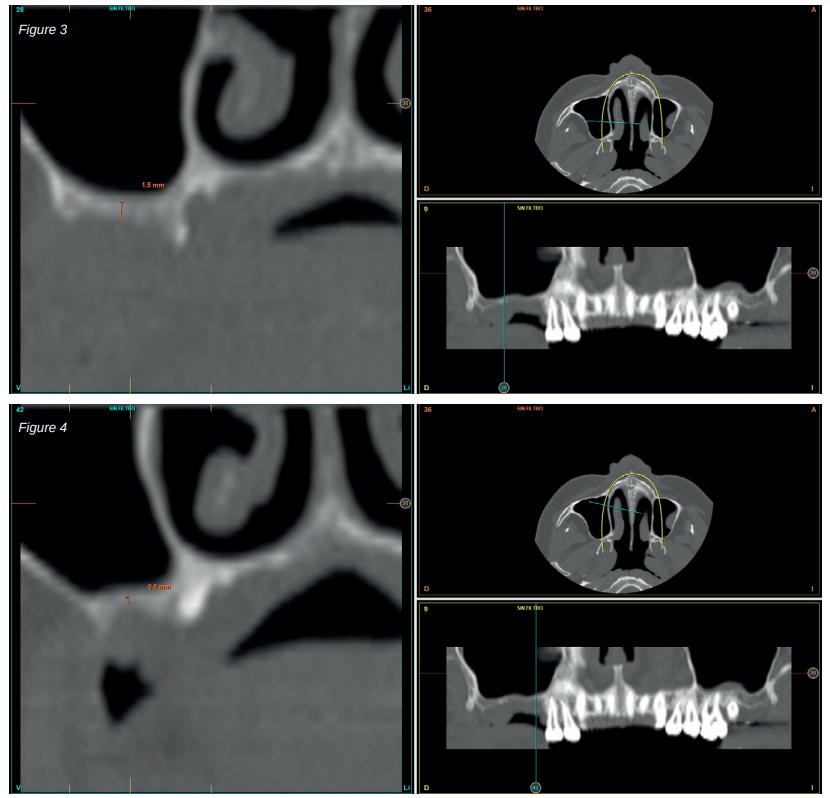

After two months, the dental cone-beam showed the perforation had closed completely but the residual bone volume provided 2 mm of bone height only, which was insufficient to insert the implants (Figures 3 and 4).

Therefore, it was decided to carry out a sinus lift using biomaterial (bovine hydroxyapatite) bound to PRGFEndoret. The elevation was performed and after five months a new dental cone beam displayed the quantity and quality of the graft obtained for the insertion of dental implants. In the cuts corresponding to the molars of the first quadrant, we observed excellent consolidation of the graft with space to insert 13 mm implants. Today, we would not choose this implant length, since studies published by our group with short and extra-short implants support their use, in addition to showing their diameter is more important than the length to distribute the loads of an already integrated implant; where an 8.5 mm length implant would work in the same way as a 13 mm implant of the same diameter18.